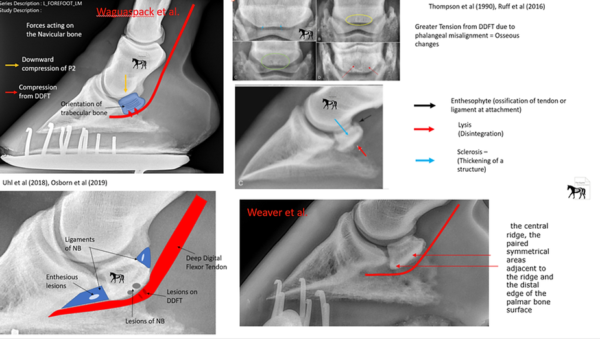

Palmar Angles

There is much debate about the ideal angle for the pedal bone to sit at in relation to the ground. … Continue reading Palmar Angles